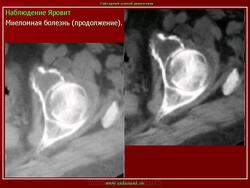

продолжение.

Миеломная болезнь